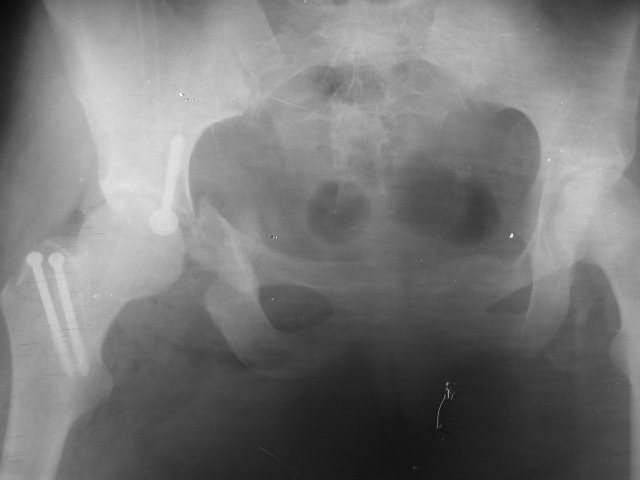

Вот что вышло! Вывих вправить проблем не составило, попопетели слегка и всё. Но поперечный перелом при попытке репозиции не двигался. После

вправления вывиха дефект задней стенки способствовал к релюксации. Чтоб этого избежать, заднюю стенку сформировали из остеотомированного фрагмента задне-нижней смещенной части вертлужной впадины. Фиксировав его одним лишь винтом. И хотя на ретнгене кажется, что операция заключалась в проведении лишь одного винта, на самом деле очень долго выкраиваили и примощали сфоормированнный отломок. Но своих целей мы достигли: вывих вправили, заднюю стенку сформировали, короче, сустав к эндопротезированию подготовили.

Кликните для загрузки файла P1010022.JPG

42KB (43296 bytes)